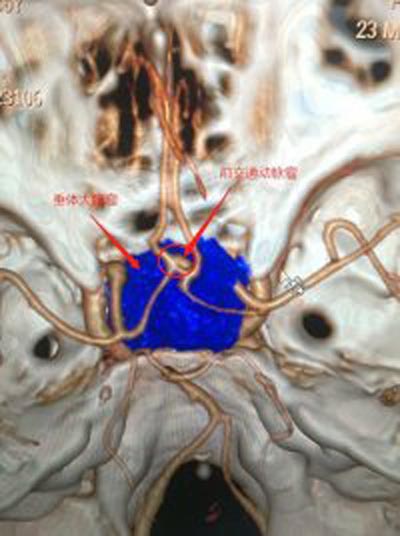

56岁的张先生,3天前出现间歇性头晕,伴有夜间尿多,当地医院就诊,头颅CT检查发现有颅内占位。广东三九脑科医院头颅MRI示:鞍区巨大垂体腺瘤伴瘤卒中,大小约4.3cm×3.1cm×2.8cm,邻近双侧颈内动脉及双侧大脑前动脉受压移位,右侧颈内动脉部分被包绕,视交叉明显受压上抬并向前移位。头颅CTA示大脑前交通囊状动脉瘤,大小约4.6mm×3.4mm。

▲术前CTA